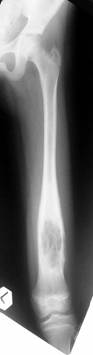

Follow Up

Consolidation regenerated

Leg length equalised but with different knee height